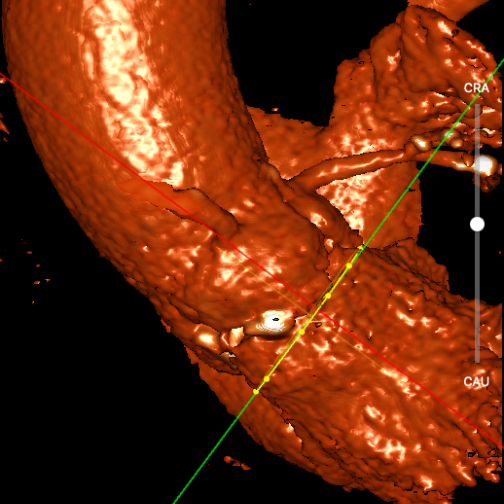

术者采用患者右侧主入路,顺利完成导丝和猪尾跨瓣等准备工作。进Landerquist超硬导丝,采用25mm球囊进行预扩,仔细评估冠脉风险后,决定对冠脉采取保护措施。根据球囊扩张情况,术中决定使用金仕生物的ProStyle预装干瓣TAV32。打开包装后,很迅速的完成了瓣膜和系统植入前的准备。输送过程系统和瓣膜轻松过弓并顺利跨瓣;开始初步释放,然后快速起搏下释放,发现位置略高后进行回收,重新定位后最终成功完成释放。反复造影发现冠脉存在阻塞风险,武汉协和团队按照风险预案在左冠植入4.0*18mm支架进行保护。术后显示左右冠脉血液灌注通畅,术后超声测量峰值流速1.45m/s,峰值压差8mmHg,几乎无瓣周漏。入路闭合顺利,无心脏及血管并发症,手术成功。

再回收后释放,术中冠脉评估

术后评估